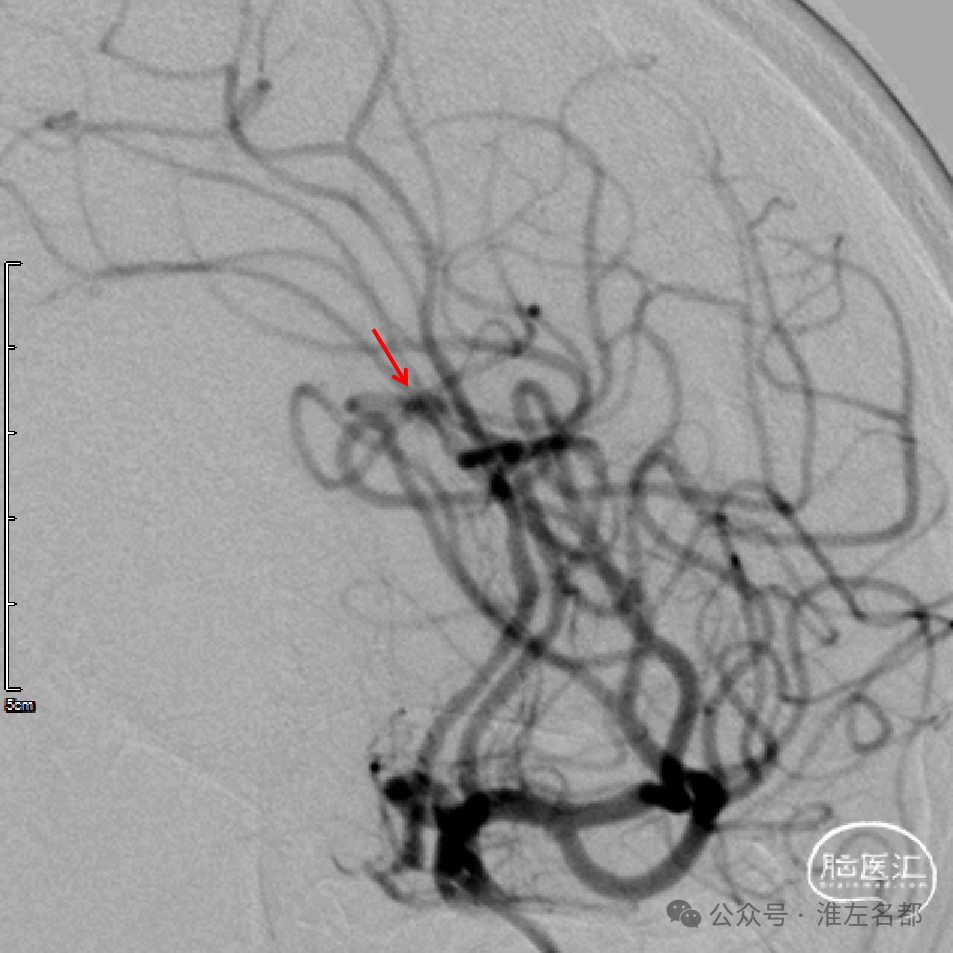

回收取栓支架后造影:闭塞再通,右侧A2局部轻微狭窄,但A3-4交界处可见造影剂渗出,提示出血。

予以降压等处理,约5分钟后造影提示出血已经停止。

术中DSA平板CT示:前纵裂旁少量蛛网膜下腔出血。

在这个患者,取栓后造影显示局部有渗血,考虑是A3-4交界处分支小血管取栓过程中受牵拉而撕裂出血,所幸的是出血很少,且很快停止。这也是中远段颅内动脉闭塞取栓操作需要谨慎的地方。中-远端血管取栓,行程远,血管管腔小,管壁薄弱,当前很多常规取栓操作技术在处理此类闭塞时可能增加出血风险,故发展新的器械和操作策略是必要的。